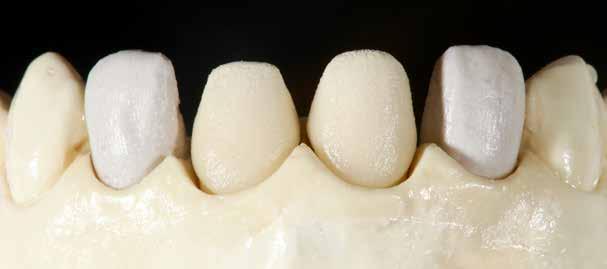

A szakirodalomban fellelhető eredmények alapján kerámia héjak ragasztására a kontaminációtól mentes, frissen vágott zománc felszín a legalkalmasabb. A hosszú távú sikeresség elérésének további feltétele a fogak konzervatív módon történő preparálása, továbbá a ragasztás kofferdám felhelyezésével biztosított, abszolút izolálásban történő kivitelezése. Úgy véljük, hogy a fenti faktorok biztosították a cikkben bemutatásra kerülő esetek – 5 évvel az átadás után megfigyelhető – sikerességét. A kofferdám izolálás alkalmazása számos előnyt biztosít a gyakorló fogorvos számára. Megakadályozza a munkaterület nyállal, vérrel, vagy szulkusz-váladékkal történő kontaminációját, és javítja a kezelendő területre való rálátásunkat. A fogak kerámia héjak ragasztása előtt történő izolálása azonban gyakran kihívást jelenthet a kevesebb klinikai tapasztalattal rendelkező fogorvosok számára. Jelen esetbemutatásban ismertetjük a kofferdám felhelyezésének lépéseit és néhány olyan gyakorlati tanácsot, amelyek jelentősen megkönnyíthetik a munkánkat, azokban az esetekben, amikor a második kisőrlőfogak közti területet kívánjuk kofferdám segítségével izolálni. A kofferdám kapcsok segítségével került rögzítésre, majd fogakat körülvevő széleit óvatosan az ínybarázdába forgattuk. A kerámia héjak számára előkészített fogakra ragasztás előtt egyenként kapcsokat helyeztünk annak érdekében, hogy a kerámia héjak rögzítése ideális körülmények között történhessen. A lépések részletes ismertetése segítséget jelenthet – a kevesebb klinikai tapasztalattal rendelkező fogorvosok számára – az abszolút izolálás megvalósításához szükséges lágyrészmenedzsment megértéséhez. Ezek az ismeretek rendkívül hasznosak lehetnek, ha a jövőben a kerámia héjak ragasztását megfelelő módon megvalósított kofferdám izolálás mellett kívánják kivitelezni. A cikkben ismertetett módszerek alkalmazásával az abszolút izolálás megvalósítható, a gumilepedő – vérzés nélkül – ínybarázdába történő beforgatására, és a ragasztáshoz szükséges idő csökkentésére.

Az előzetes állapotfelmérést és a kezelés megtervezését követően a fogakat minimál invazív módon preparáltuk (1. a-b ábrák), majd az előkészített fogak ínybarázdáiba fonalbehelyező eszköz segítségével (113 Serrated Gingival Cord Packer, Hu-Friedy, Chicago, Illinois) teflonszalagot helyeztünk (Loctite Thread Seal Tape, Henkel Loctite Corp., Egyesült Államok), (1. c ábra). A hagyományos retrakciós fonalak helyett, a rugalmasságuk miatt előnyösebbnek tartjuk a teflonszalagok használatát. A kofferdámot (Dental Dam, Nic Tone, Bukarest, Románia) az előkészített fogakon kívül, az azoktól disztálisan elhelyezkedő egy-egy fognak megfelelően is perforáltuk.

Az általunk alkalmazott adhezív rendszerek hatékonyságát nagymértékben növelhetjük azáltal, hogy a fogakat minimál invazív módon, azaz csak zománcon belül preparáljuk, és a kerámia héjakat kofferdám izolálásban ragasztjuk. Jelen esetismertetésünknek az volt a célja, hogy bemutassuk, hogyan lehet az adekvát módon kivitelezett kofferdám izolálással megelőzni

a munkaterület nyállal, vérrel vagy szulkusz-váladékkal történő kontaminációját. A megfelelő méretben kialakított perforációs nyílások és köztük lévő optimális távolság elengedhetetlen ahhoz, hogy a kofferdámot ideális módon tudjuk felhelyezni. Ezzel az esettel azt is bizonyítjuk, hogy a gumilepedő levegőfújással, fogselyemmel és teflonszalagok segítségével történő beforgatásával az ínyvérzés kialakulását el lehet kerülni. Ismételten szeretnénk hangsúlyozni, hogy a megfelelő kofferdám kapcsok használata nélkül nem tudtuk volna a preparált csonkszélt a gumilepedő szélétől eltartani. A kezelés során elért eredményeket jól alátámasztotta, hogy a páciens az ötéves kontroll vizsgálat során teljesen elégedett volt.